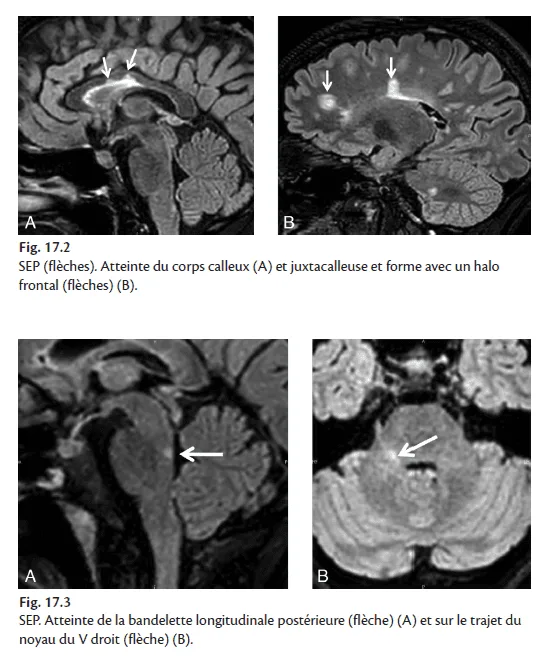

Les lésions cérébrales. Situées quasi exclusivement dans la substance blanche, elles sont en hypersignal FLAIR et T2. Leurs caractéristiques sont détaillées dans l'encadré 17.1. Certaines localisations sont très évocatrices : partie inférieure du corps calleux – la lésion triangulaire lui donnant un aspect crénelé (fig. 17.2) –, pédoncules cérébelleux supérieur et moyen, bandelette longitudinale postérieure responsable d'une OIN (ophtalmoplégie internucléaire), lésion sous-corticale ou parfois corticale en coup d'ongle (fig. 17.3 et 17.4). À noter que des lésions thalamiques peuvent se voir, le thalamus comportant de nombreuses fibres de substance blanche.

Figure 17.2 & Figure 17.3